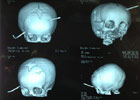

Hình chụp sọ não cháu bé 10 tháng tuổi bị thanh sắt dài đâm xuyên qua

Theo lời kể của gia đình bệnh nhi, ngày 19.8, Nhi đang được ba bế đứng chơi ngoài sân thì không may bị một thanh sắt từ máy cắt cỏ mà người hàng xóm đang sử dụng bay văng đâm xuyên qua đầu.

Bác sĩ Chung cho biết, bé nhập viện trong tình trạng lơ mơ và có thanh sắt dài đâm xuyên từ bên này qua bên kia đầu.

Các bác sĩ đã nhanh chóng chẩn đoán bệnh nhi bị vết thương sọ não do dị vật đâm xuyên, gây tổn thương vỏ não và nhu mô não trên đường thanh sắt đi qua."Đây là một tổn thương rất nặng và cực kỳ nguy hiểm", bác sĩ Chung đánh giá.

Hình chụp CT đầu cháu bé sau phẫu thuật